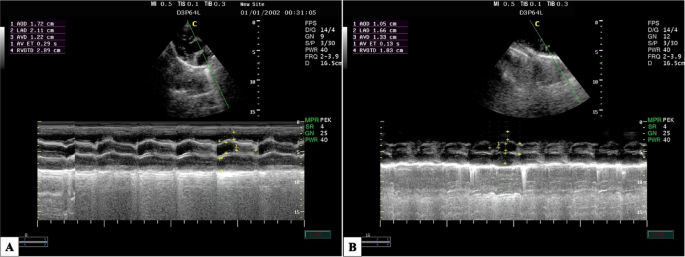

Furthermore, the following parameters were assessed: the mean arterial blood pressure (MAP), heart rate (HR), respiratory frequency (fR), oxygen saturation of hemoglobin (SpO2), end-tidal carbon dioxide concentration (EtCO2), and rectal temperature (RT) were measured at previous time points using a multi-parameter monitor (Aisys Carestation, General Electric Co; Datex-Ohmeda, GE Healthcare Inc., Madison, WI, USA). Additionally, the echocardiographic examination was conducted using portable ultrasonographic equipment (Esaote MylabTM 30 Vet Gold, Brazil) with a sectoral transducer (PA240) at a frequency range of 1 to 4 MHz. These parameters were assessed at different time points: before the administration of pre-anesthetic medications considered as a baseline (M0); 30 min after the administration of pre-anesthetic medications (M1); immediately after intubation (M2); and at 10, 20, 30, 40, and 50 min after maintaining anesthesia (T10, T20, T30, T40, and T50).

The dogs were placed in right lateral recumbent positions, and echocardiographic measurements followed the guidelines outlined in the literature40,41,42,43,44,45. In the right parasternal window, on the transverse axis, the following parameters were evaluated using M mode: diastolic and systolic interventricular septum thickness (IVSd and IVSs cm), diastolic and systolic left ventricular internal diameter (LVIDd and LVIDs cm), left ventricular posterior wall thickness at end-diastole and end-systole (LVPWd and LVPWs cm), interventricular septal thickness at end-diastole and end-systole (IVSTd and IVSTs cm), left ventricular volume at end-diastole and end-systole (EDV and ESV ml). The stroke volume (SV ml), fractional shortening percentage (FS%), ejection fraction percentage (EF%), and the left atrial/aortic diameter ratio (La/Ao ratio) were calculated from the measurements performed in M mode.

The effects of acepromazine/methadone, ketofol, and atracurium/ketofol during the experimental period on the echocardiographic parameters between the groups and within the same group are presented (Table 2). Echocardiography findings of SV, EF%, and FS% were significantly affected by the time for ketofol (P = 0.012) and atracurium/ketofol (P = 0.031) compared with the post-sedation period M1. However, the AKFG recorded significantly higher values (P ≤ 0.05) of SV, EF%, and FS% at M2 compared with the KFG during the maintenance period of anesthesia.

The cardiac parameters, such as FS%, EF%, and SV, exhibited significant changes until the end of the anaesthetic period (P ≤ 0.05) in dogs that received the AKFG compared to the KFG. The most significant difference between the M1 and T10 was observed when atracurium and ketamine were administered via bolus injection. Interestingly, the wall thickness did not rapidly increase, suggesting that ventricular myocardial fibers in postnatal dogs tend to elongate more than they widen. Another possibility is that myocardial density increases with age while extracellular water concentration decreases. In addition, age had a significant impact on the mean values of left ventricular posterior wall thickness (LVPWs) and interventricular septal thickness at end-diastole (IVSd)74.